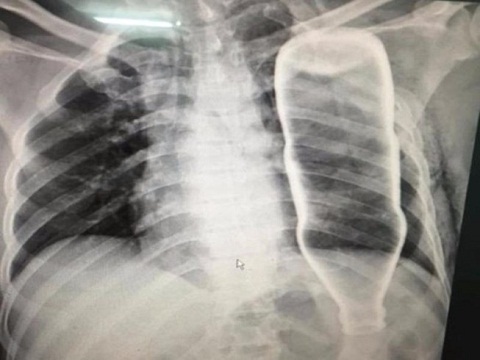

Hi hữu: Bệnh nhân bị cả chai thủy tinh chui vào lồng ngực

Ngã từ cầu thang, người đàn ông bị cả chai nước lớn chui vào lồng ngực và làm gãy hai xương sườn.